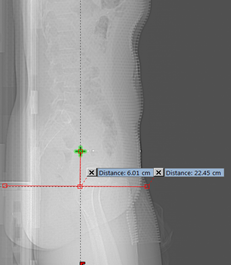

Anteroposterior (AP) Dimension: The AP dimension is thickness (anterior to posterior dimension) of the body part being scanned. The AP dimensions of the patient were measured from lateral localizer radiograph as shown in Figure 2. The AP dimensions were also measured on sagittal plane of 3D reconstructed data where maximum dimension occurs to compare its efficacy against localizer radiograph.

Figure 2 Measurement of AP dimension.